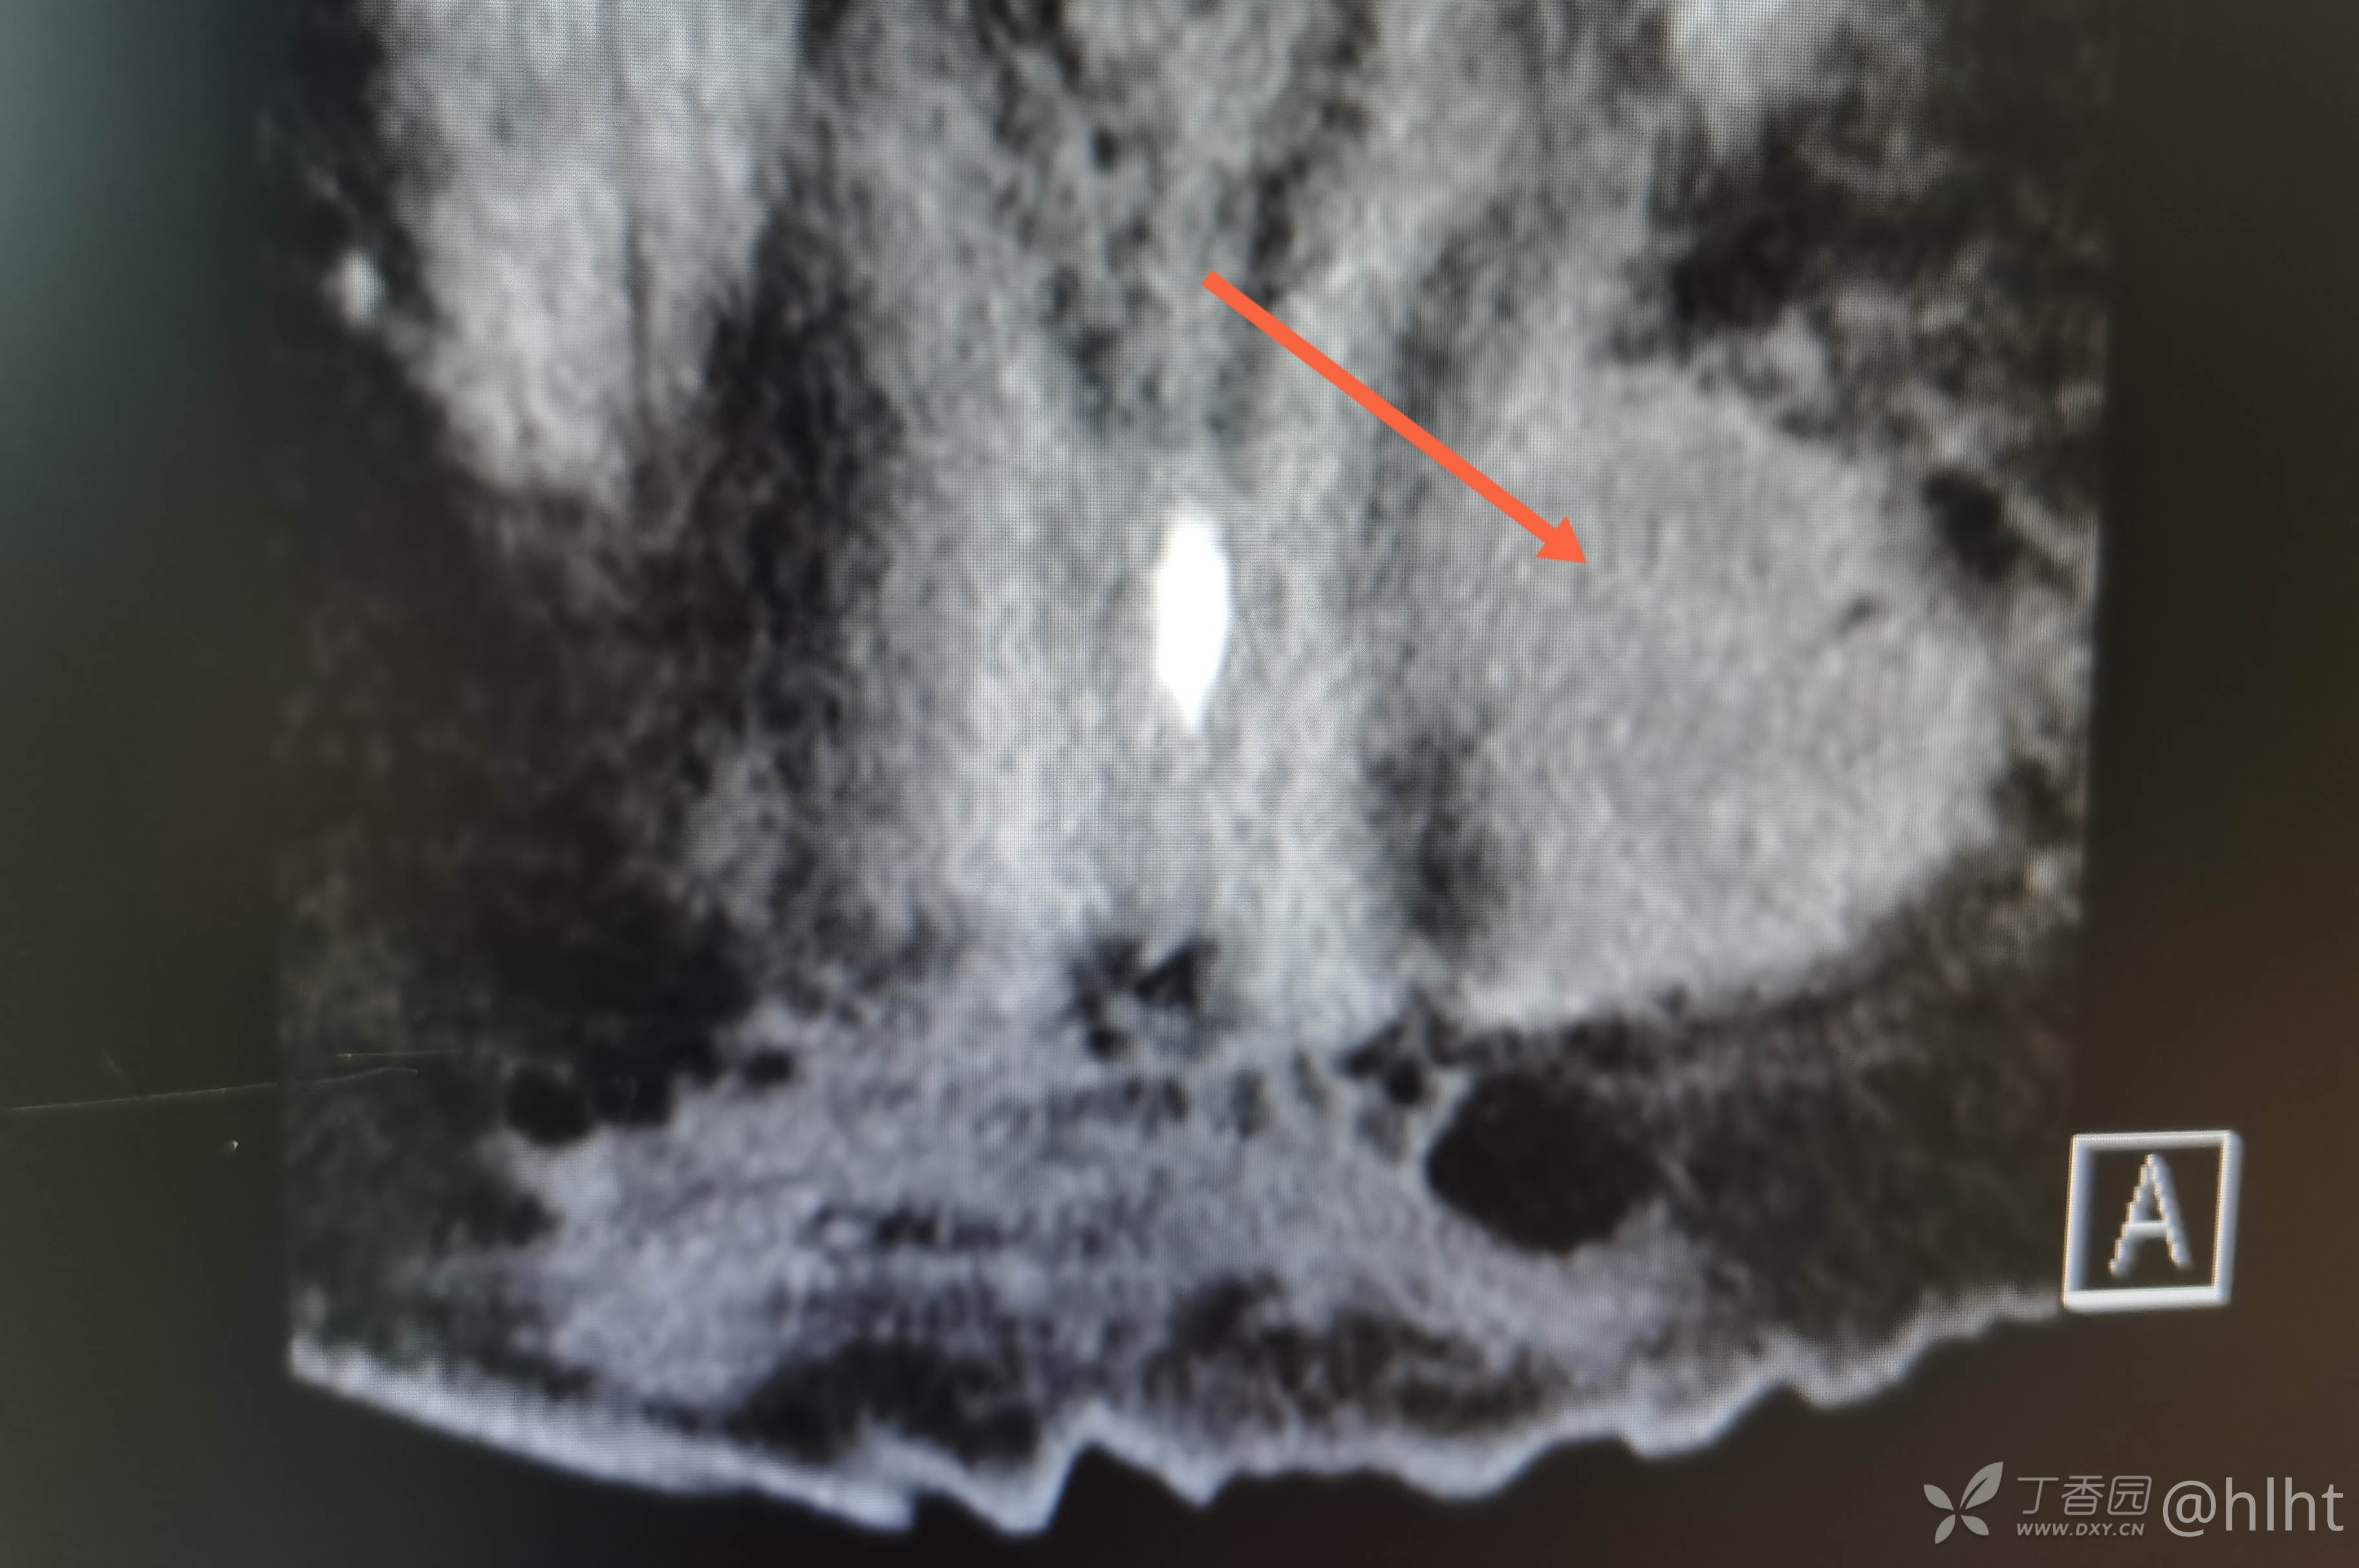

诊断:1.左侧腰大肌、髂腰肌脓肿 :结核? 2.2型糖尿病 3.高血压2级